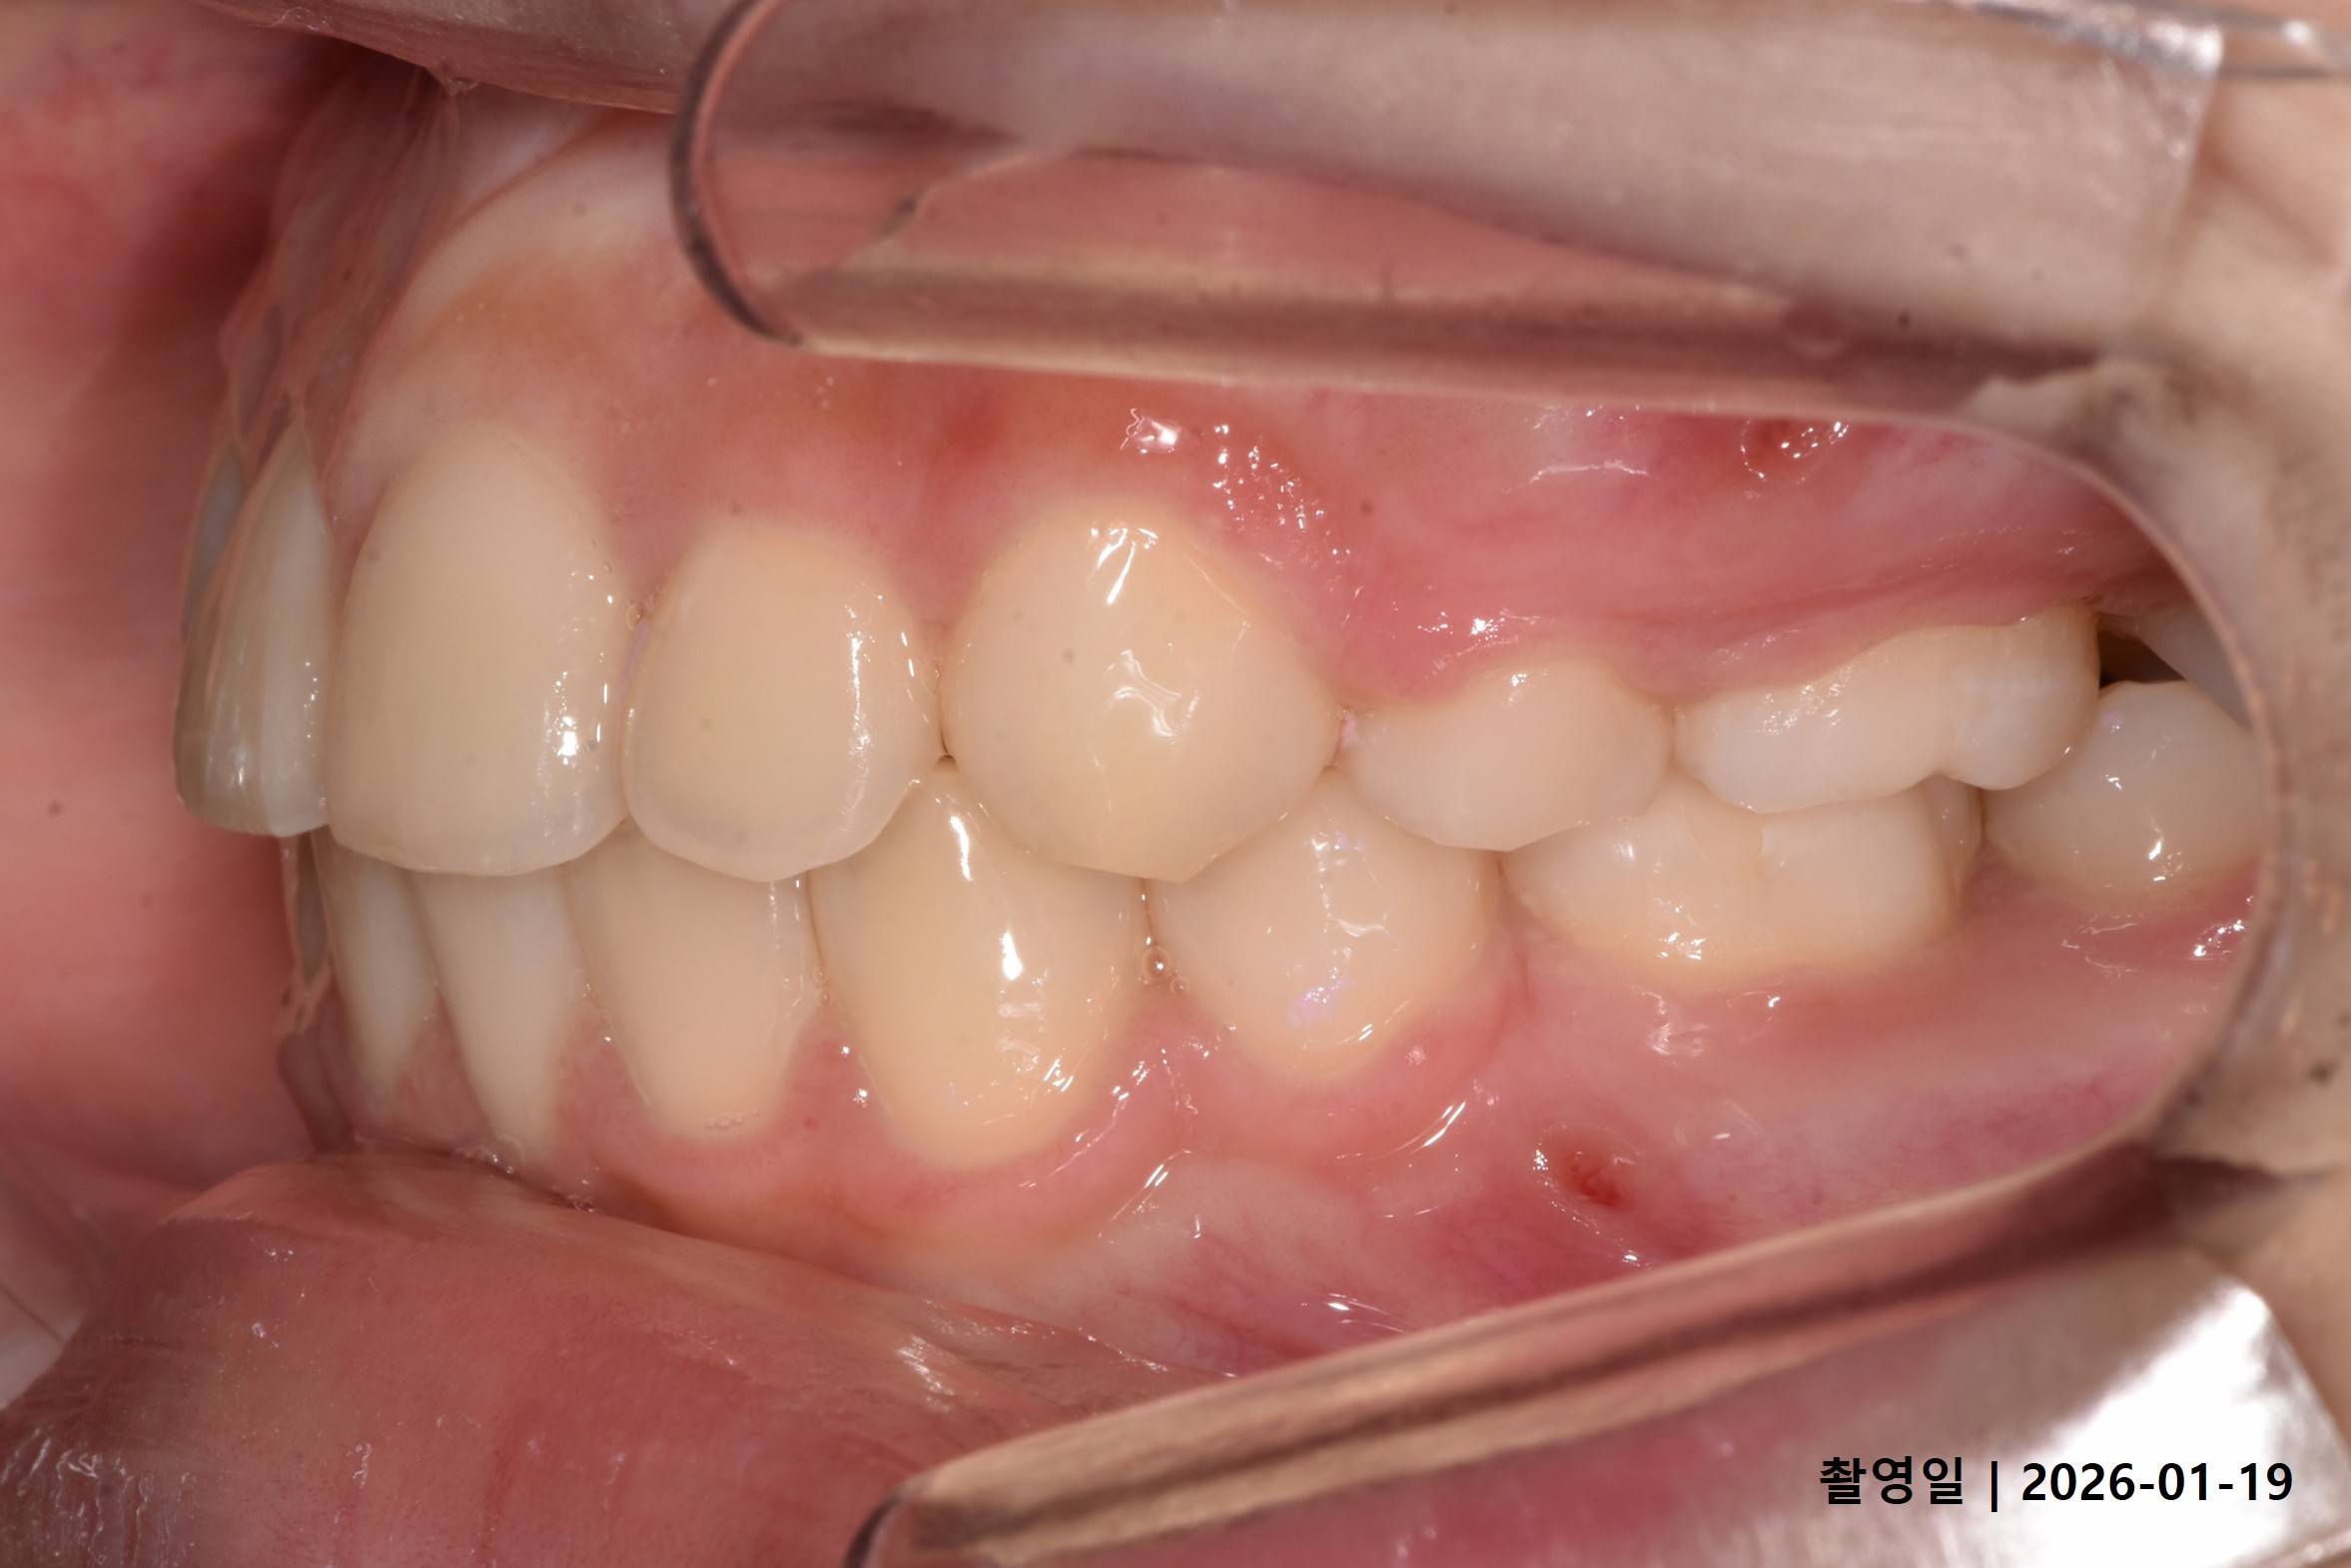

Case 2

- 24세 여성

- 상하악소구치 발치

- 치료기간 2년 1개월

치료 전

치료 후